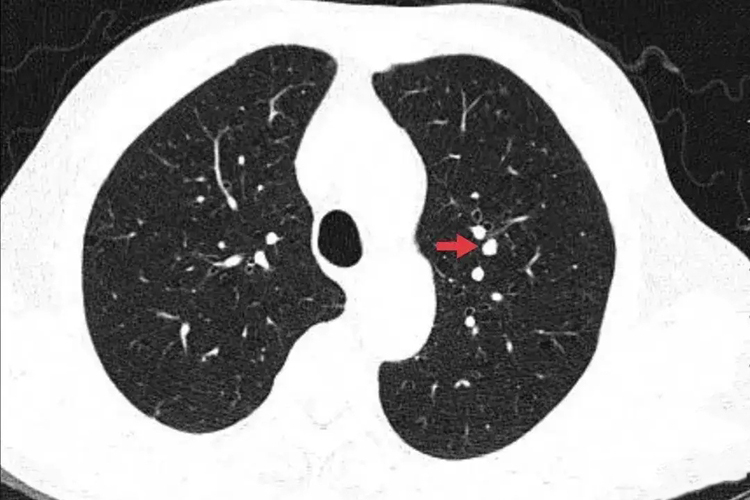

肺结节多是指在接受胸部CT或者X线拍片检查时,发现在肺部出现直径≤30mm的近似圆形或不规则形状的病灶,这种病灶的边界清晰或不清晰,在影像学上表现为密度增高的阴影,可以是单发也可以是多发。

对于直径较小的肺结节,可给予6-12个月一次的随访,如果结节无变化,也可5年复查2次。对于部分可疑结节,如实质性成分增多或结节增大,则需要考虑手术切除治疗,并于5年内每年进行一次复查。